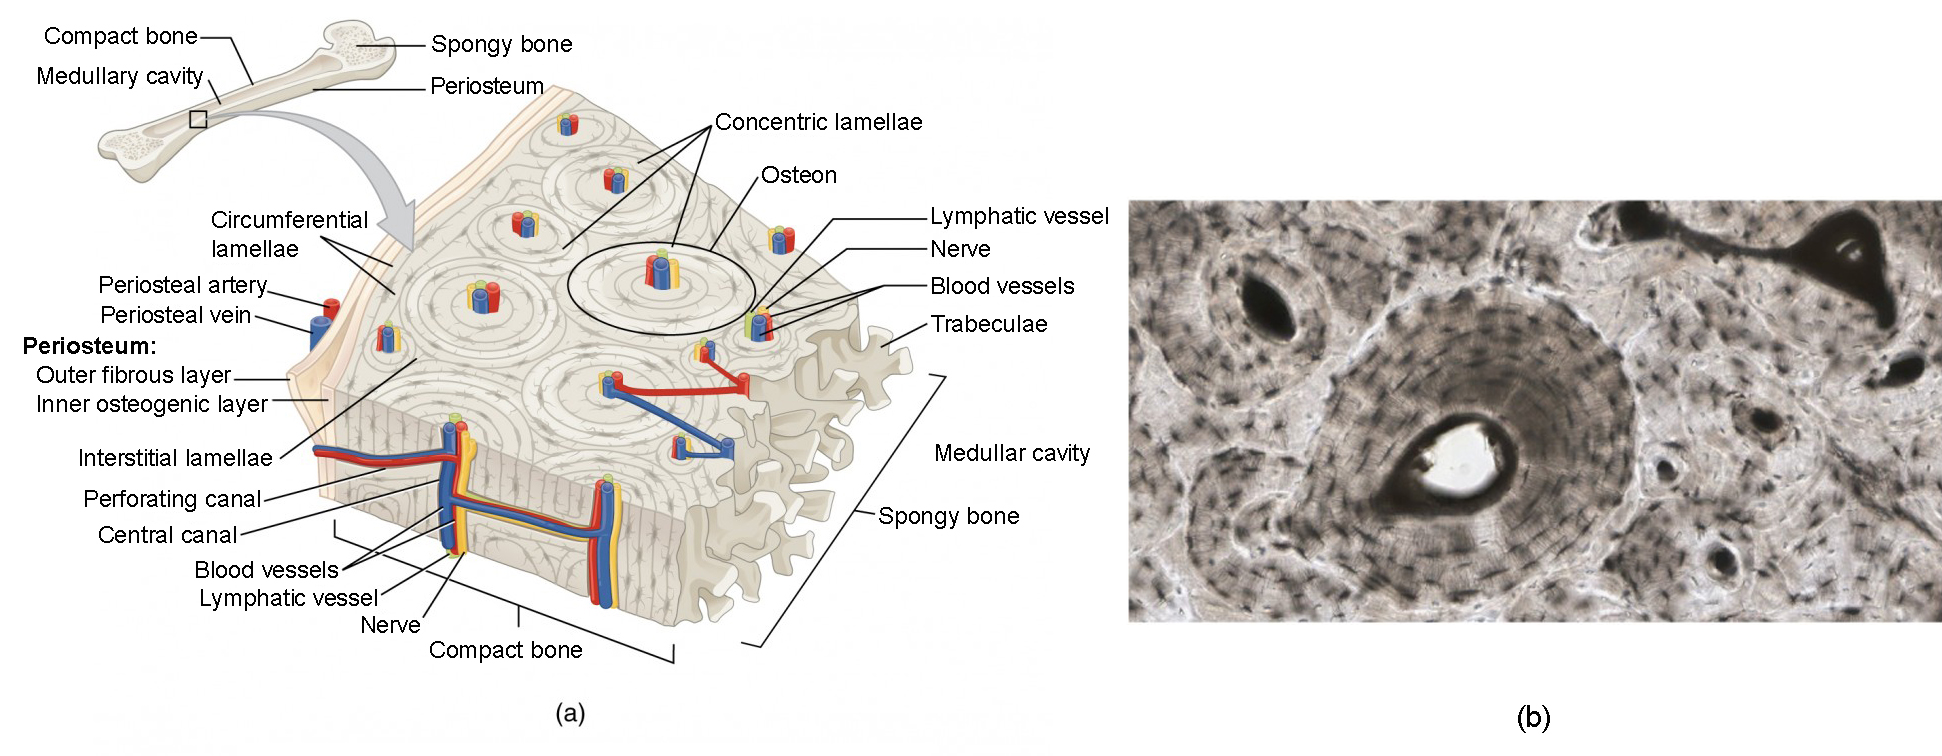

Структура грубоволокнистой костной ткани: наглядные примеры